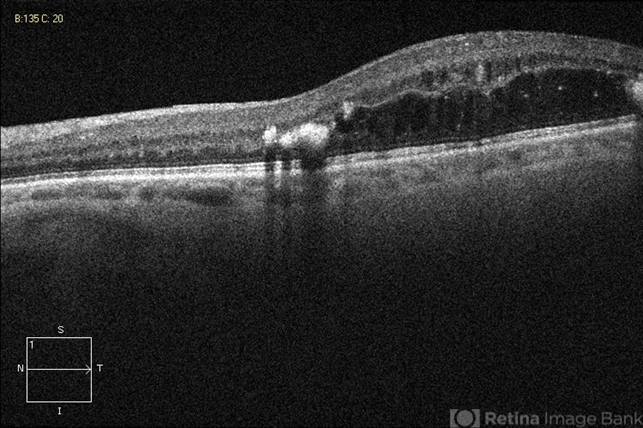

- circinate ring

- Optical coherence tomography system

- DR; hard exudate at edges of macular edema and are hyper-reflective with shadowing.